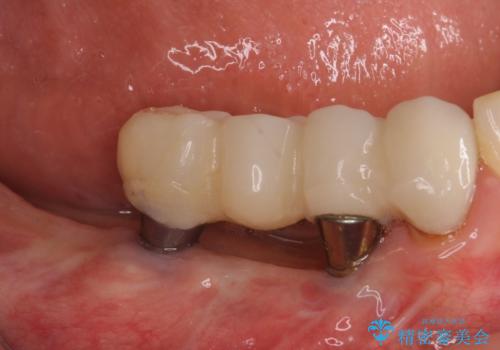

下顎右側は骨造成を併用してインプラント治療を行い、その他の奥歯もインプラントや歯周外科処置を併用して補綴治療を進め、最後に前歯部の欠けてしまったセラミッククラウンを作り替えることとしました。